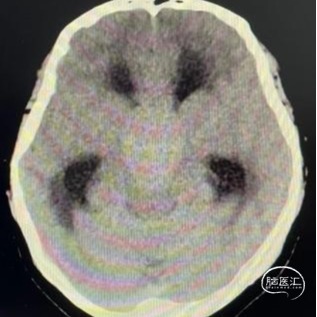

头部CT平扫显示:全鞍型蝶窦,鞍区-鞍上区-第三脑室可见一混杂密度肿块,内可见多发钙化灶,最大层面大小约43mm*35mm(左右径-前后径),CT值30HU,双侧脑室明显扩张,室旁可见对称性条片状低密度灶。